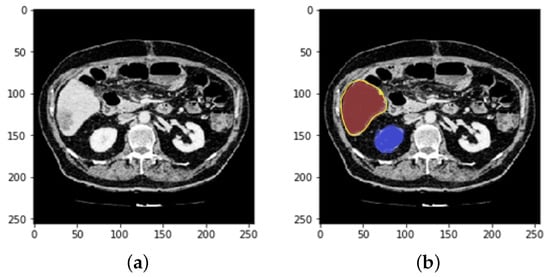

4.1. Segmentation Process of Liver and Liver Tumor